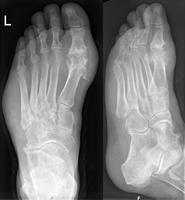

Gout may be diagnosed and treated without further investigations in someone with hyperuricemia and the classic acute arthritis of the base of the great toe (known as podagra). Synovial fluid analysis should be done if the diagnosis is in doubt.[15][46] Plain X-rays are usually normal and are not useful for confirming a diagnosis of early gout.[8] They may show signs of chronic gout such as bone erosion.[42]